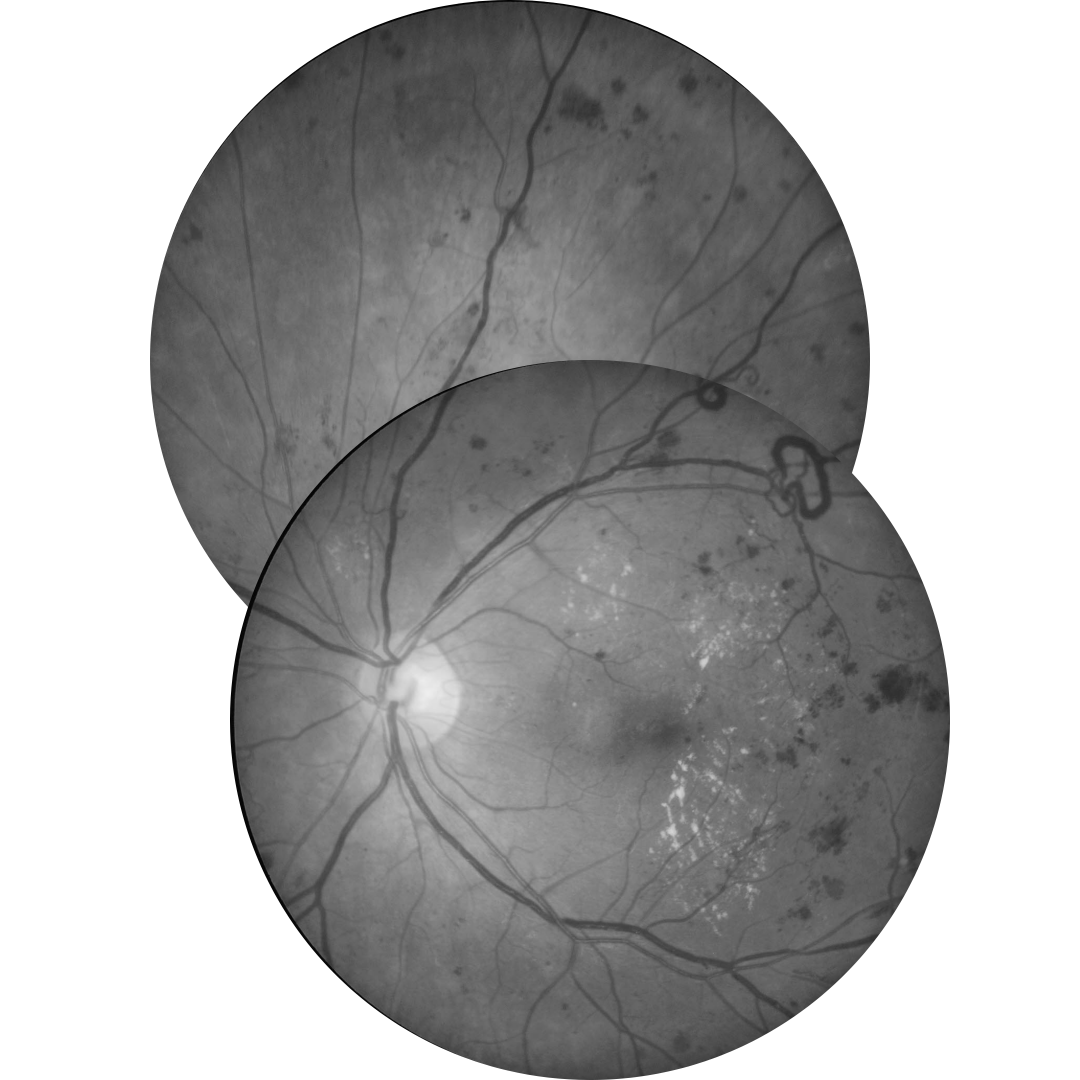

Below is a summary and examples of different lesions associated with diabetic retinopathy.

Lesions of Proliferative Diabetic Retinopathy

Retinal neovascularisation

Neovascularisation (NV) appears as new vessels which loop back around or form a disorganised network above the retinal surface, distinguishing them from normal capillaries.

They are found on the surface of the internal limiting membrane (ILM) or posterior hyaloid face of the vitreous and occur at the border between perfused and ischaemic retina.

They are prone to bleeding, resulting in pre-retinal (PRH) or vitreous haemorrhage (VH). Any pre-retinal or vitreous haemorrhage should be considered as NV until proven otherwise.

Dynamic interaction between NV and the vitreous can lead to an inflammatory response and

subsequent fibrous proliferation (FP).Neovascularisation of the disc (NVD) describes new vessels on or within 1 disc diameter of the disc as opposed to neovascularisation elsewhere (NVE) outside this region.